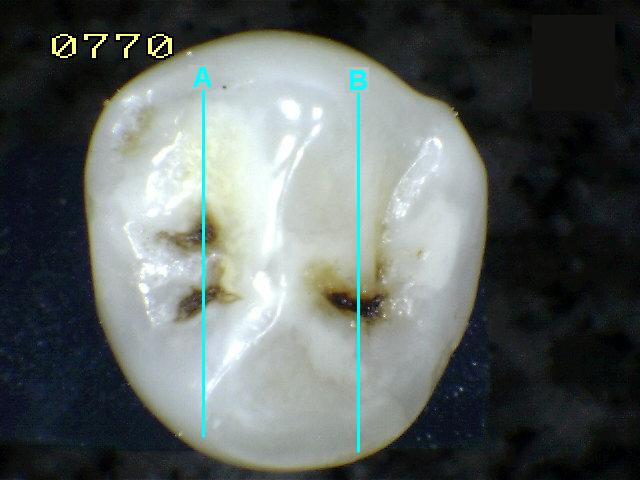

Corte en fosa mesial "A"

Corte en fosa distal "B"

Código histológico 0 en ambos cortes